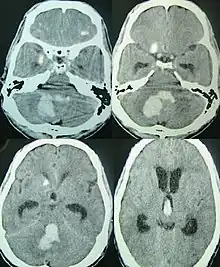

.jpg.webp) | |

| CT scan of a spontaneous intracerebral bleed, leaking into the lateral ventricles | |

Intraparenchymal hemorrhage can be recognized on CT scans because blood appears brighter than other tissue and is separated from the inner table of the skull by brain tissue. The tissue surrounding a bleed is often less dense than the rest of the brain because of edema, and therefore shows up darker on the CT scan.[30] The oedema surrounding the haemorrhage would rapidly increase in size in the first 48 hours, and reached its maximum extent at day 14. The bigger the size of the haematoma, the larger its surrounding oedema.[31] Brain oedema formation is due to the breakdown of red blood cells, where haemoglobin and other contents of red blood cells are released. The release of these red blood cells contents causes toxic effect on the brain and causes brain oedema. Besides, the breaking down of blood-brain barrier also contributes to the odema formation.[13]